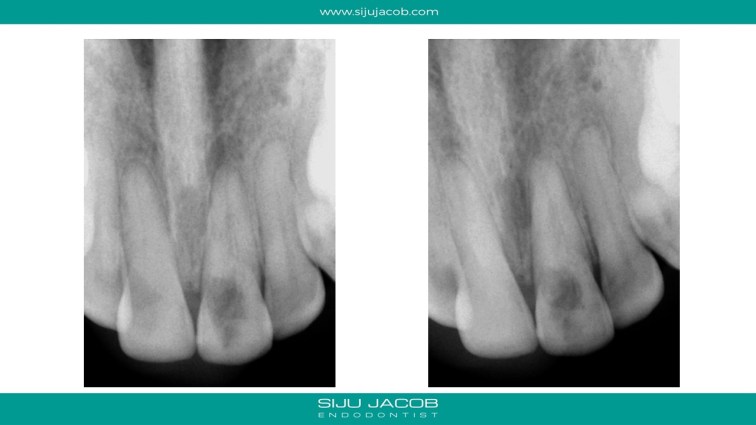

The internal resorption in this case was quite aggressive, but not perforating externally. It is always fascinating to see how much of tooth destruction happens in these cases. Even after cleaning up the soft tooth structure, the underlying hard dentine keeps flaking away and continues to have “bleeding points”. Munce burs are quite useful in cleaning up the altered dentine. By the time I cleaned up till there were no more “bleeding points”, there wasn’t much tooth structure left coronally. I put a fiber post to give some strength coronally. I treated this case before I was aware of Trichloro acetic acid (TCA).